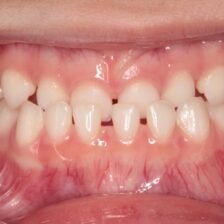

当院ではCT・マイクロスコープ・セファロなどの精密検査機器を活用し、歯を残すための選択肢をできる限りご提案します。

歯髄温存治療(MTA)や歯冠長延長術、矯正的挺出など、専門的な治療にも対応。

また、痛みに配慮した麻酔方法で、安心して治療を受けていただけます。

歯を残すための精密診断と専門治療